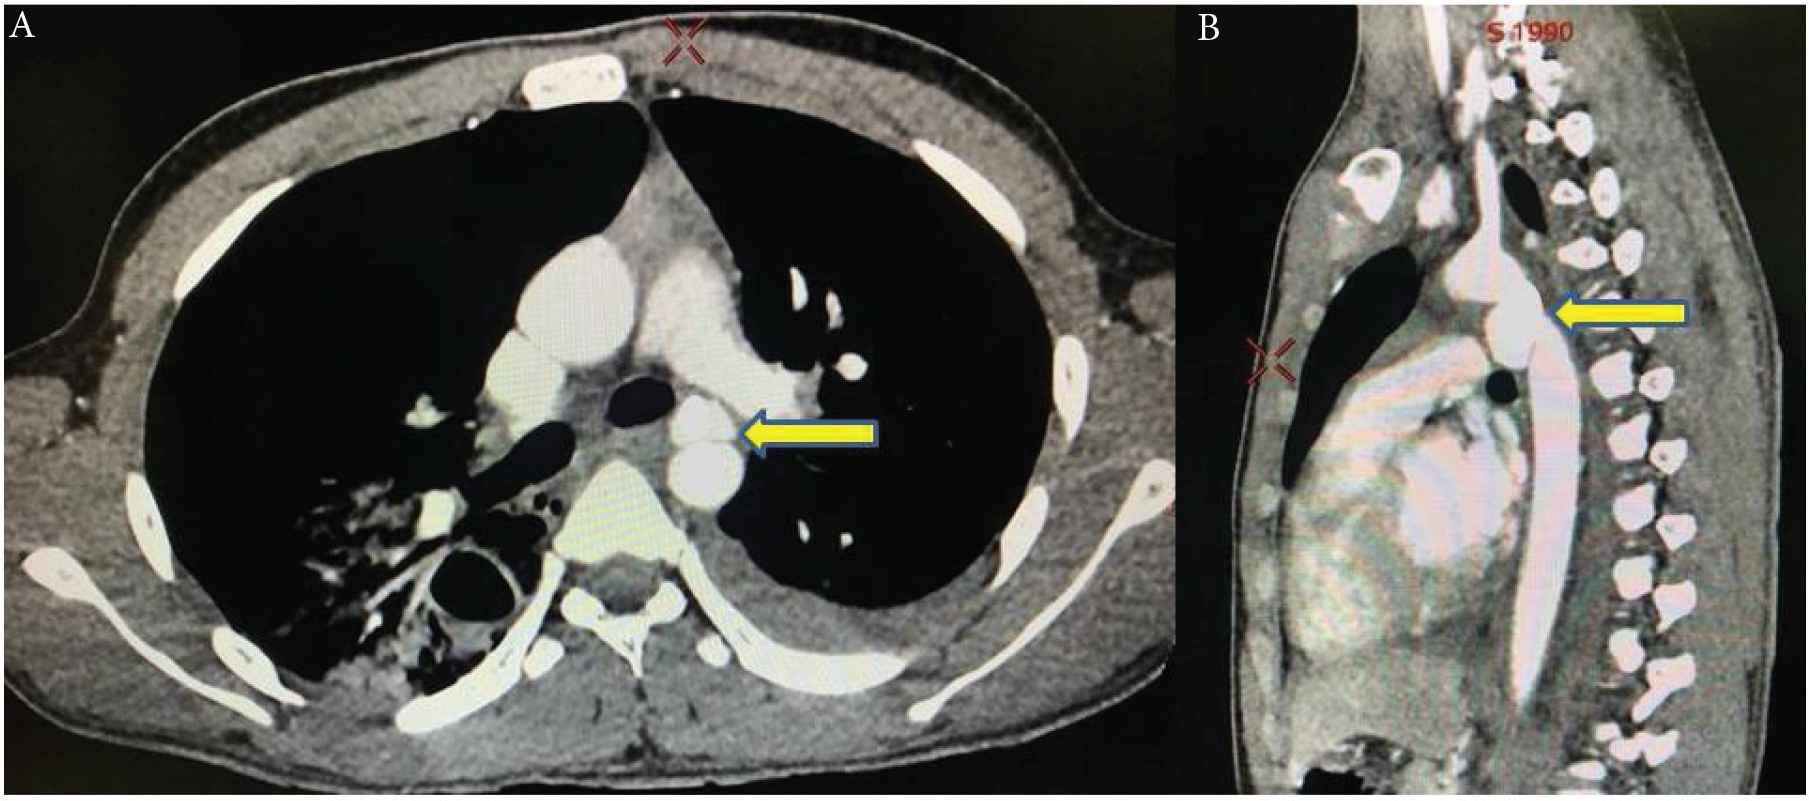

The patient has no comorbidities, but he is a known victim of a motor vehicle accident 13 months ago; he was admitted to the hospital with multiple injuries, including liver injury, bilateral hemothorax, pulmonary laceration, bilateral fractured ribs, a fractured sternum, and grade 3 BTAI with pseudoaneurysm, for which the patient was treated with TEVAR, using a Cook device 105 × 24 mm with oversizing around 20% (aorta diameter, 20.5 mm) (Cook Medical LLC, Bloomington, IN, USA). He was later discharged home in a stable condition. Post-procedure CTA was performed in the only follow-up visit, 10 days after discharge, and no early TEVAR-related complication was observed. The patient did not respond to the multiple requests for follow-up and he did not show up since his last and only visit (Figure 1).

Grade 3 traumatic aortic dissection. (A) Axial Computerized Tomography Angiography (CTA) with intimal flap causing false and true lumen. (B) Coronal CTA revealed pseudoaneurysm (yellow arrows).